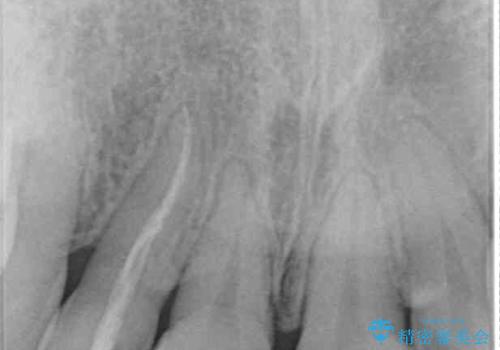

レントゲン写真より、歯根の炎症が認められなかったため、ファイバーコアによる土台築製後、オーダーメイドタイプのオールセラミッククラウンにて補綴することとしました。